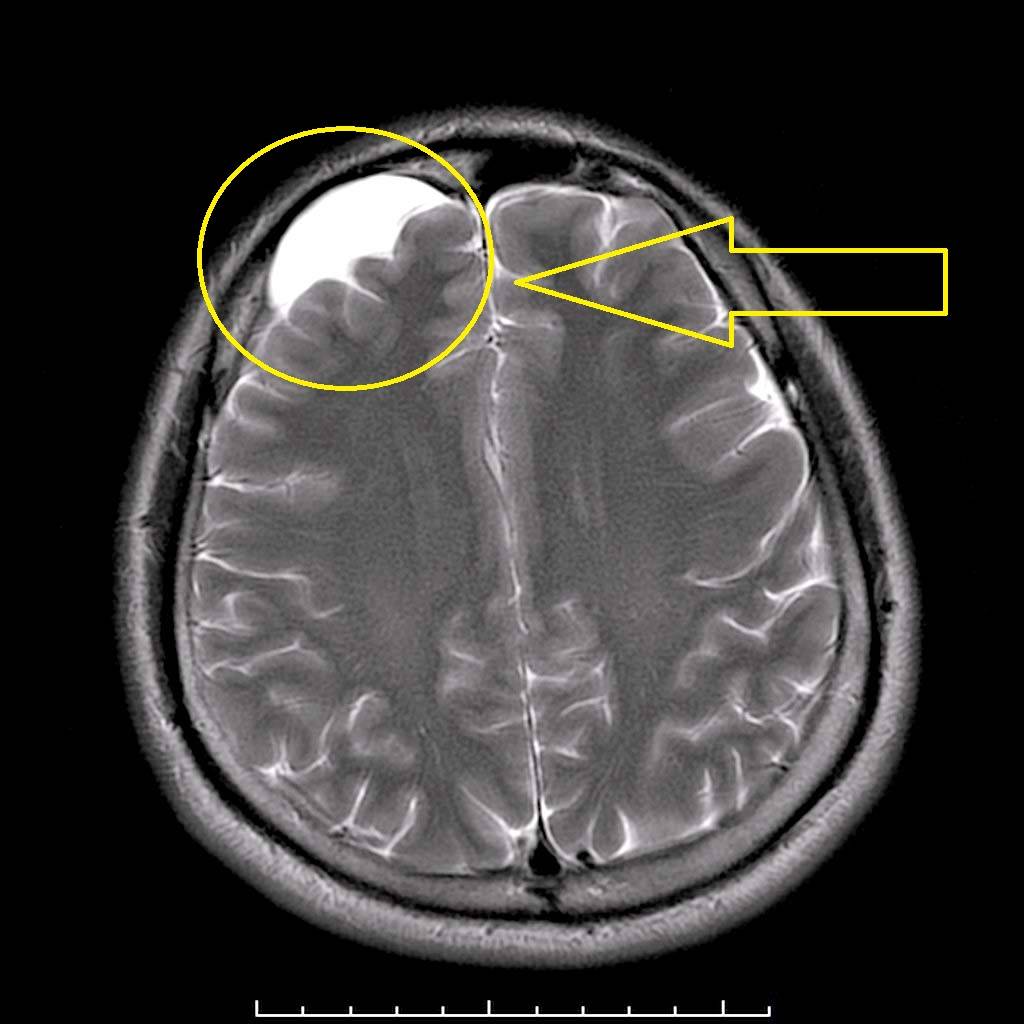

Выявление патологии.

Основной метод диагностики, который позволяет получить всю необходимую информацию о новообразовании – МРТ. При небольшом размере, отсутствии жалоб со стороны пациента можно не принимать никаких мер.

Обязательным является постоянное отслеживание динамики состояния – при кистозном расширении может понадобиться хирургическое вмешательство.